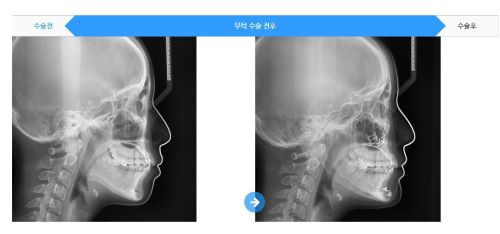

먼저 턱이 뒤로 들어가 있지만 치아의 교합이

잘 맞는 경우라면 턱끝을 앞으로 전진시켜주는

무턱수술을 통해 턱 라인을 뚜렷하게 개선이 가능합니다.

하지만 턱이 뒤로 들어가 있지만 치아 교합이

잘 맞지 않는다면 하악왜소증으로 구분되어

턱 전체를 앞으로 이동시켜주는 양악수술이 필요할 수 있으므로

자신에게 맞는 방법을 찾아보는 것이 중요합니다.